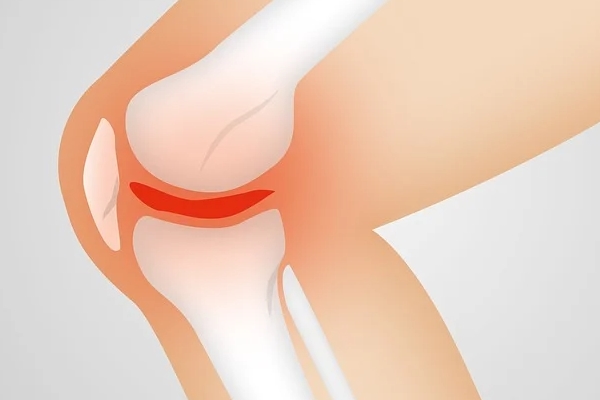

퇴행성 관절염은 관절을 보호하고 있는 연골의 점진적인 손상이나 퇴행성 변화로 인해 관절을 이루는 뼈와 인대 등에 손상이 일어나서 염증과 통증이 생기는 질환으로, 관절의 염증성 질환 중 가장 높은 빈도를 보입니다.

통증은 초기에는 해당 관절을 움직일 때 심해지는 양상을 보이다가 병이 진행되면 움직임 여부에 관계없이 지속적으로 나타나기도 하는데요. 관절 운동 범위의 감소, 종창(부종), 관절 주위의 압통이 나타나며 관절 연골의 소실과 변성에 의해 관절면이 불규칙해지면 관절 운동 시 마찰음이 느껴질 수도 있다고 합니다.